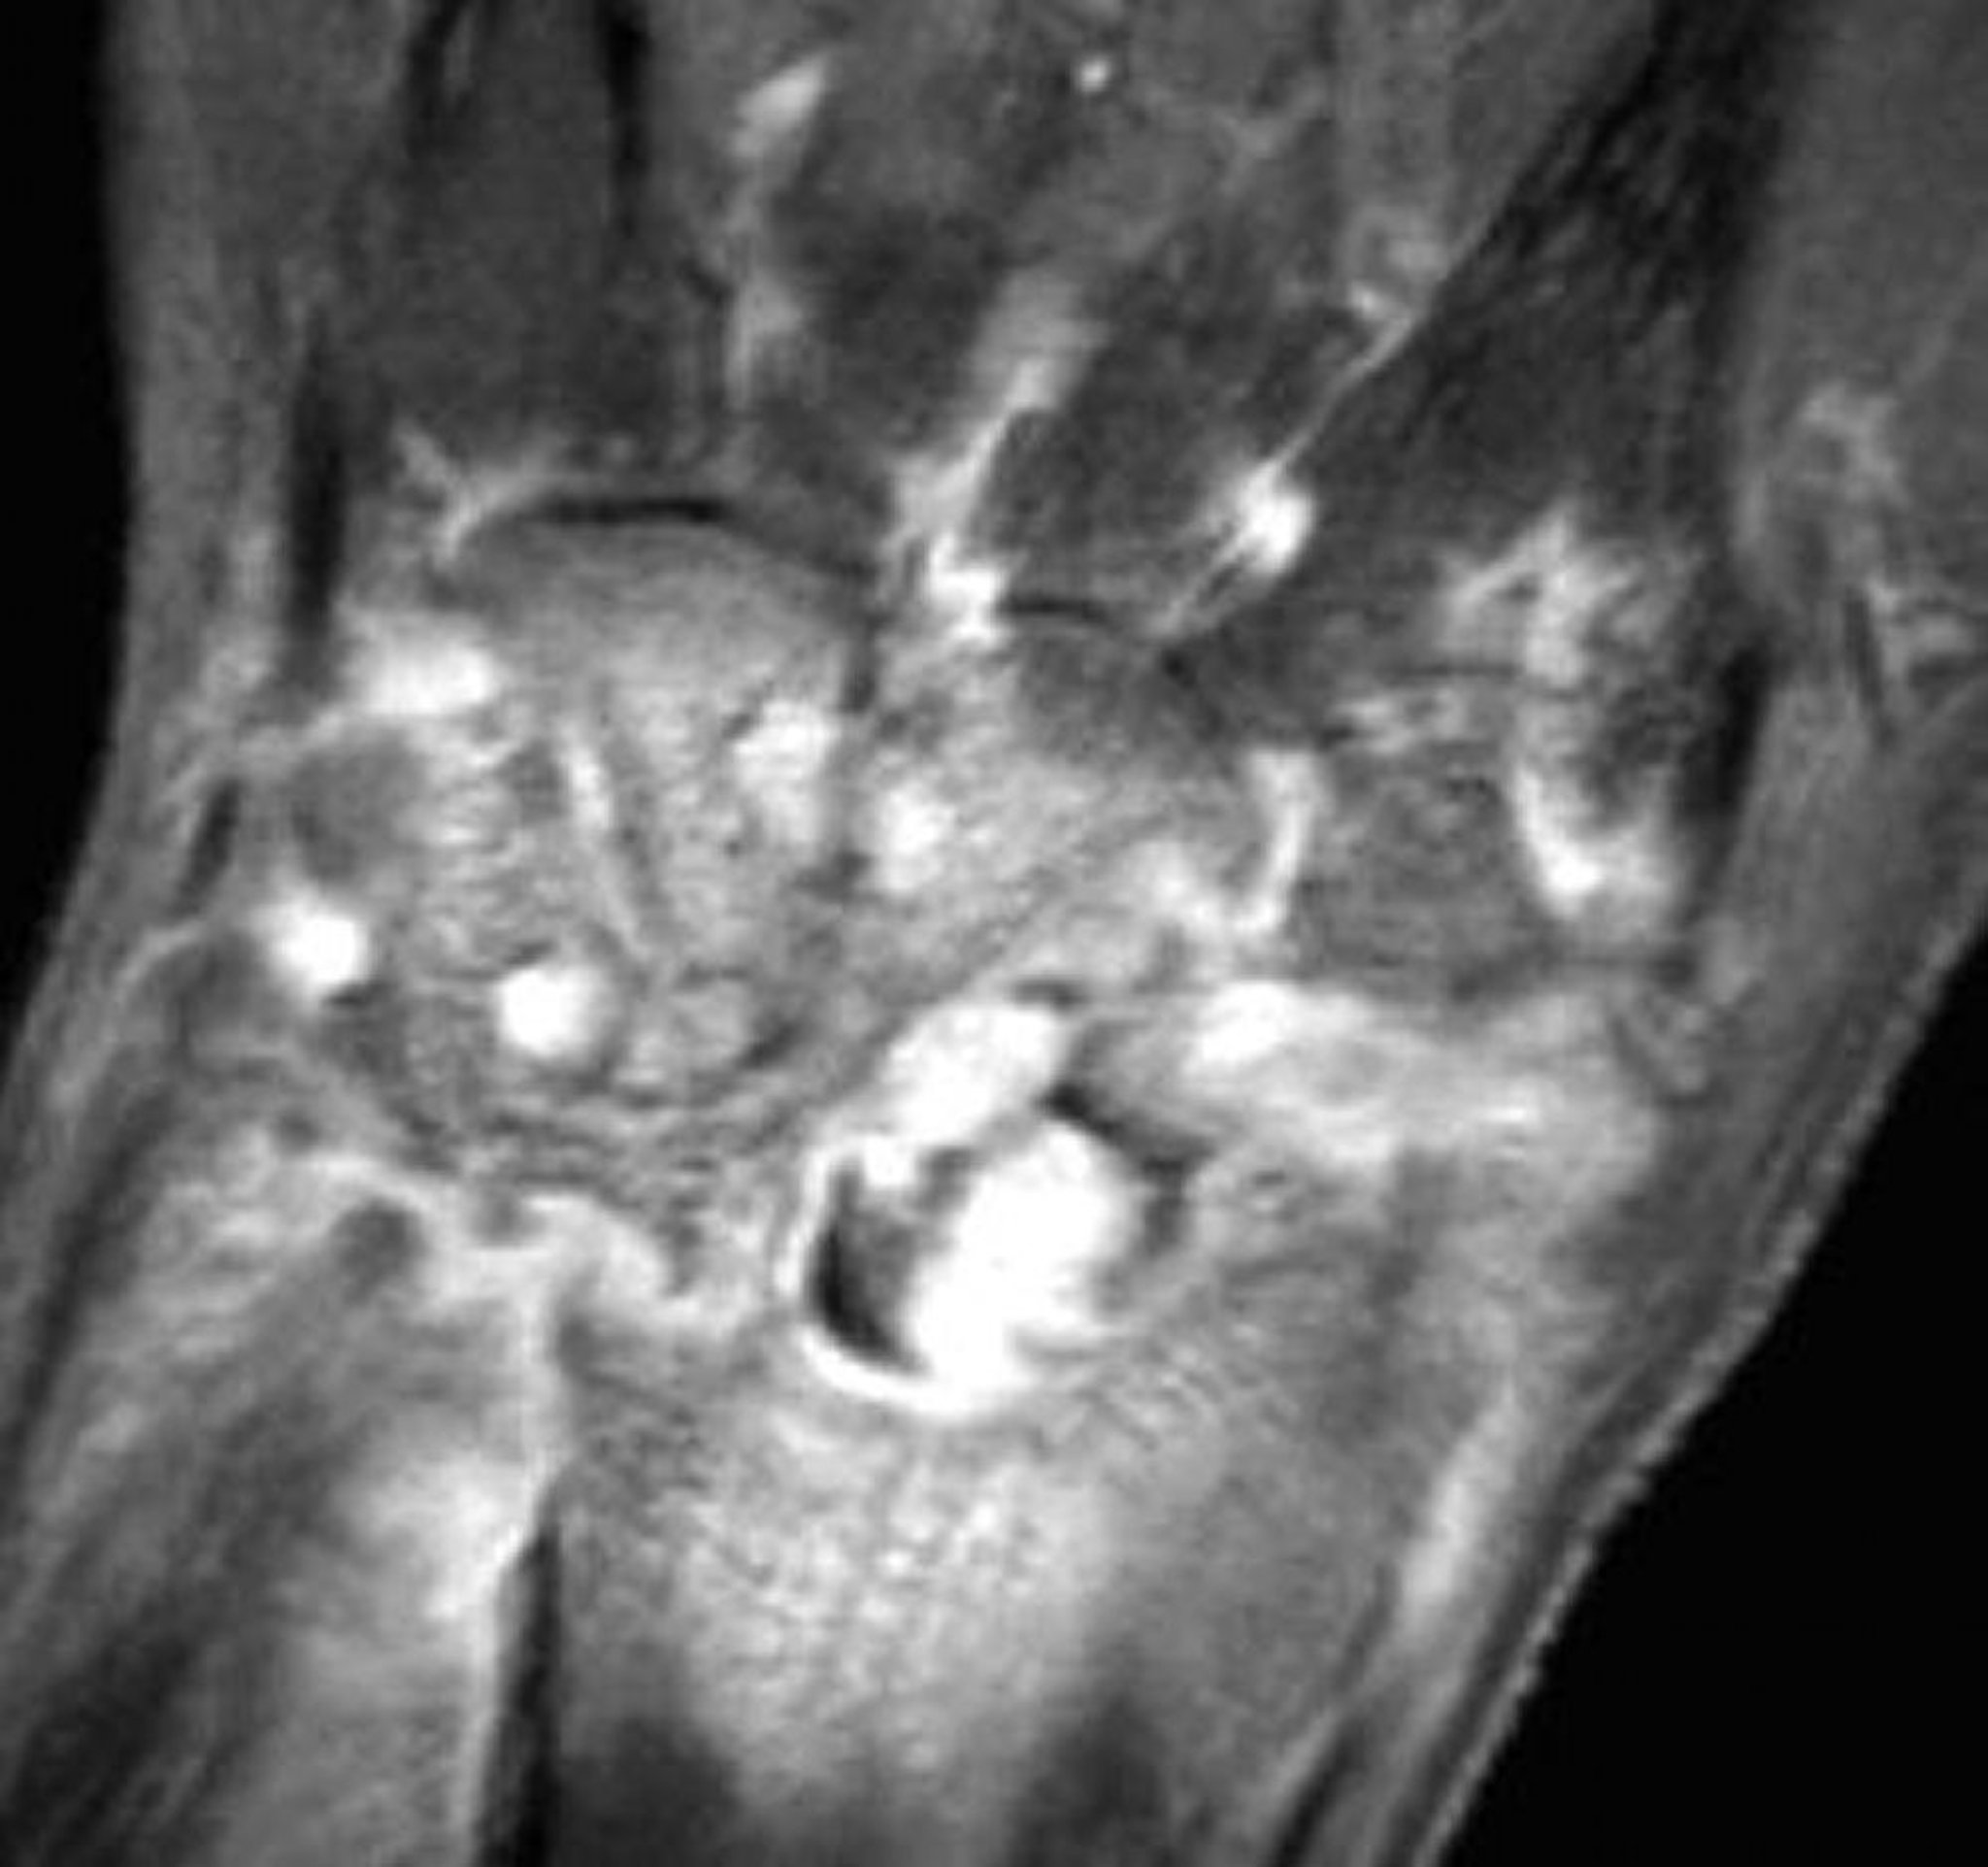

このガドリニウムを用いた脂肪抑制T1強調MRIによる淋菌性の化膿性関節炎の手関節の冠状断像では,びまん性の滑膜増強およびびらんが認められる。